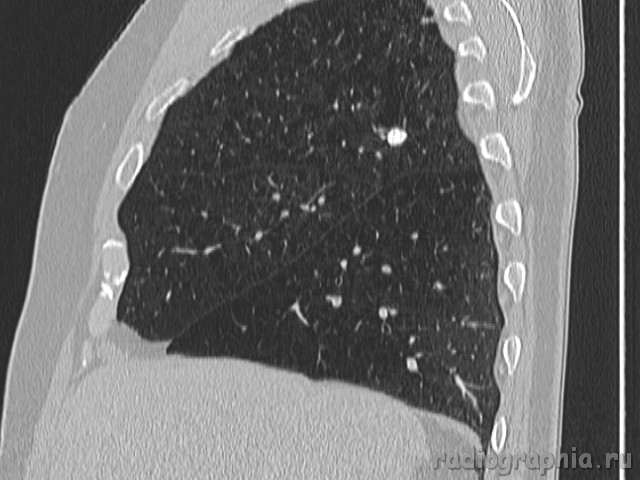

Одиночный узел правого лёгкого.

На рутинном снимке ОГК, был выявлен одиночный узел; по протоколу выполнили КТ. Какое было бы ваше заключение; и как бы Вы поступили если у вас нет возможности выполнять КТ?

Routine Chest X-Ray. SPN (solitary pulmonary nodule-red arrow)